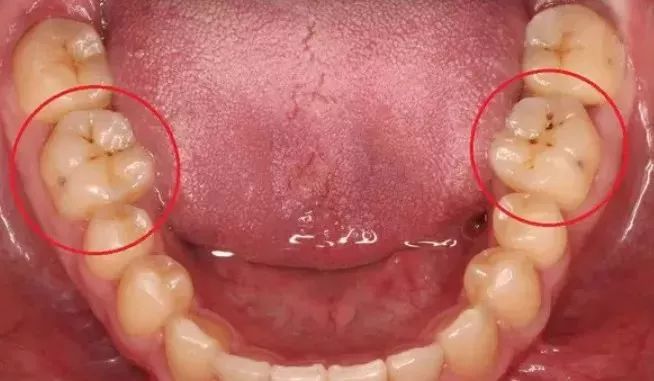

很多人照镜子时,都发现自己内侧大齿表面有一个小黑点,也不疼,就是看起来奇怪,而且怎么刷也刷不掉。

一种是色素沉着,如烟渍、茶渍、咖啡渍等。

另一种则是牙齿出现了或深或浅的龋坏。龋齿的罪魁祸首是口腔中的某些细菌,但它们破坏牙齿也是需要时间的,从初期的变色到最终形成龋洞,通常需要1年半到两年。在此期间,我们多留心自己的牙齿,完全可能把龋坏扼杀在萌芽阶段。